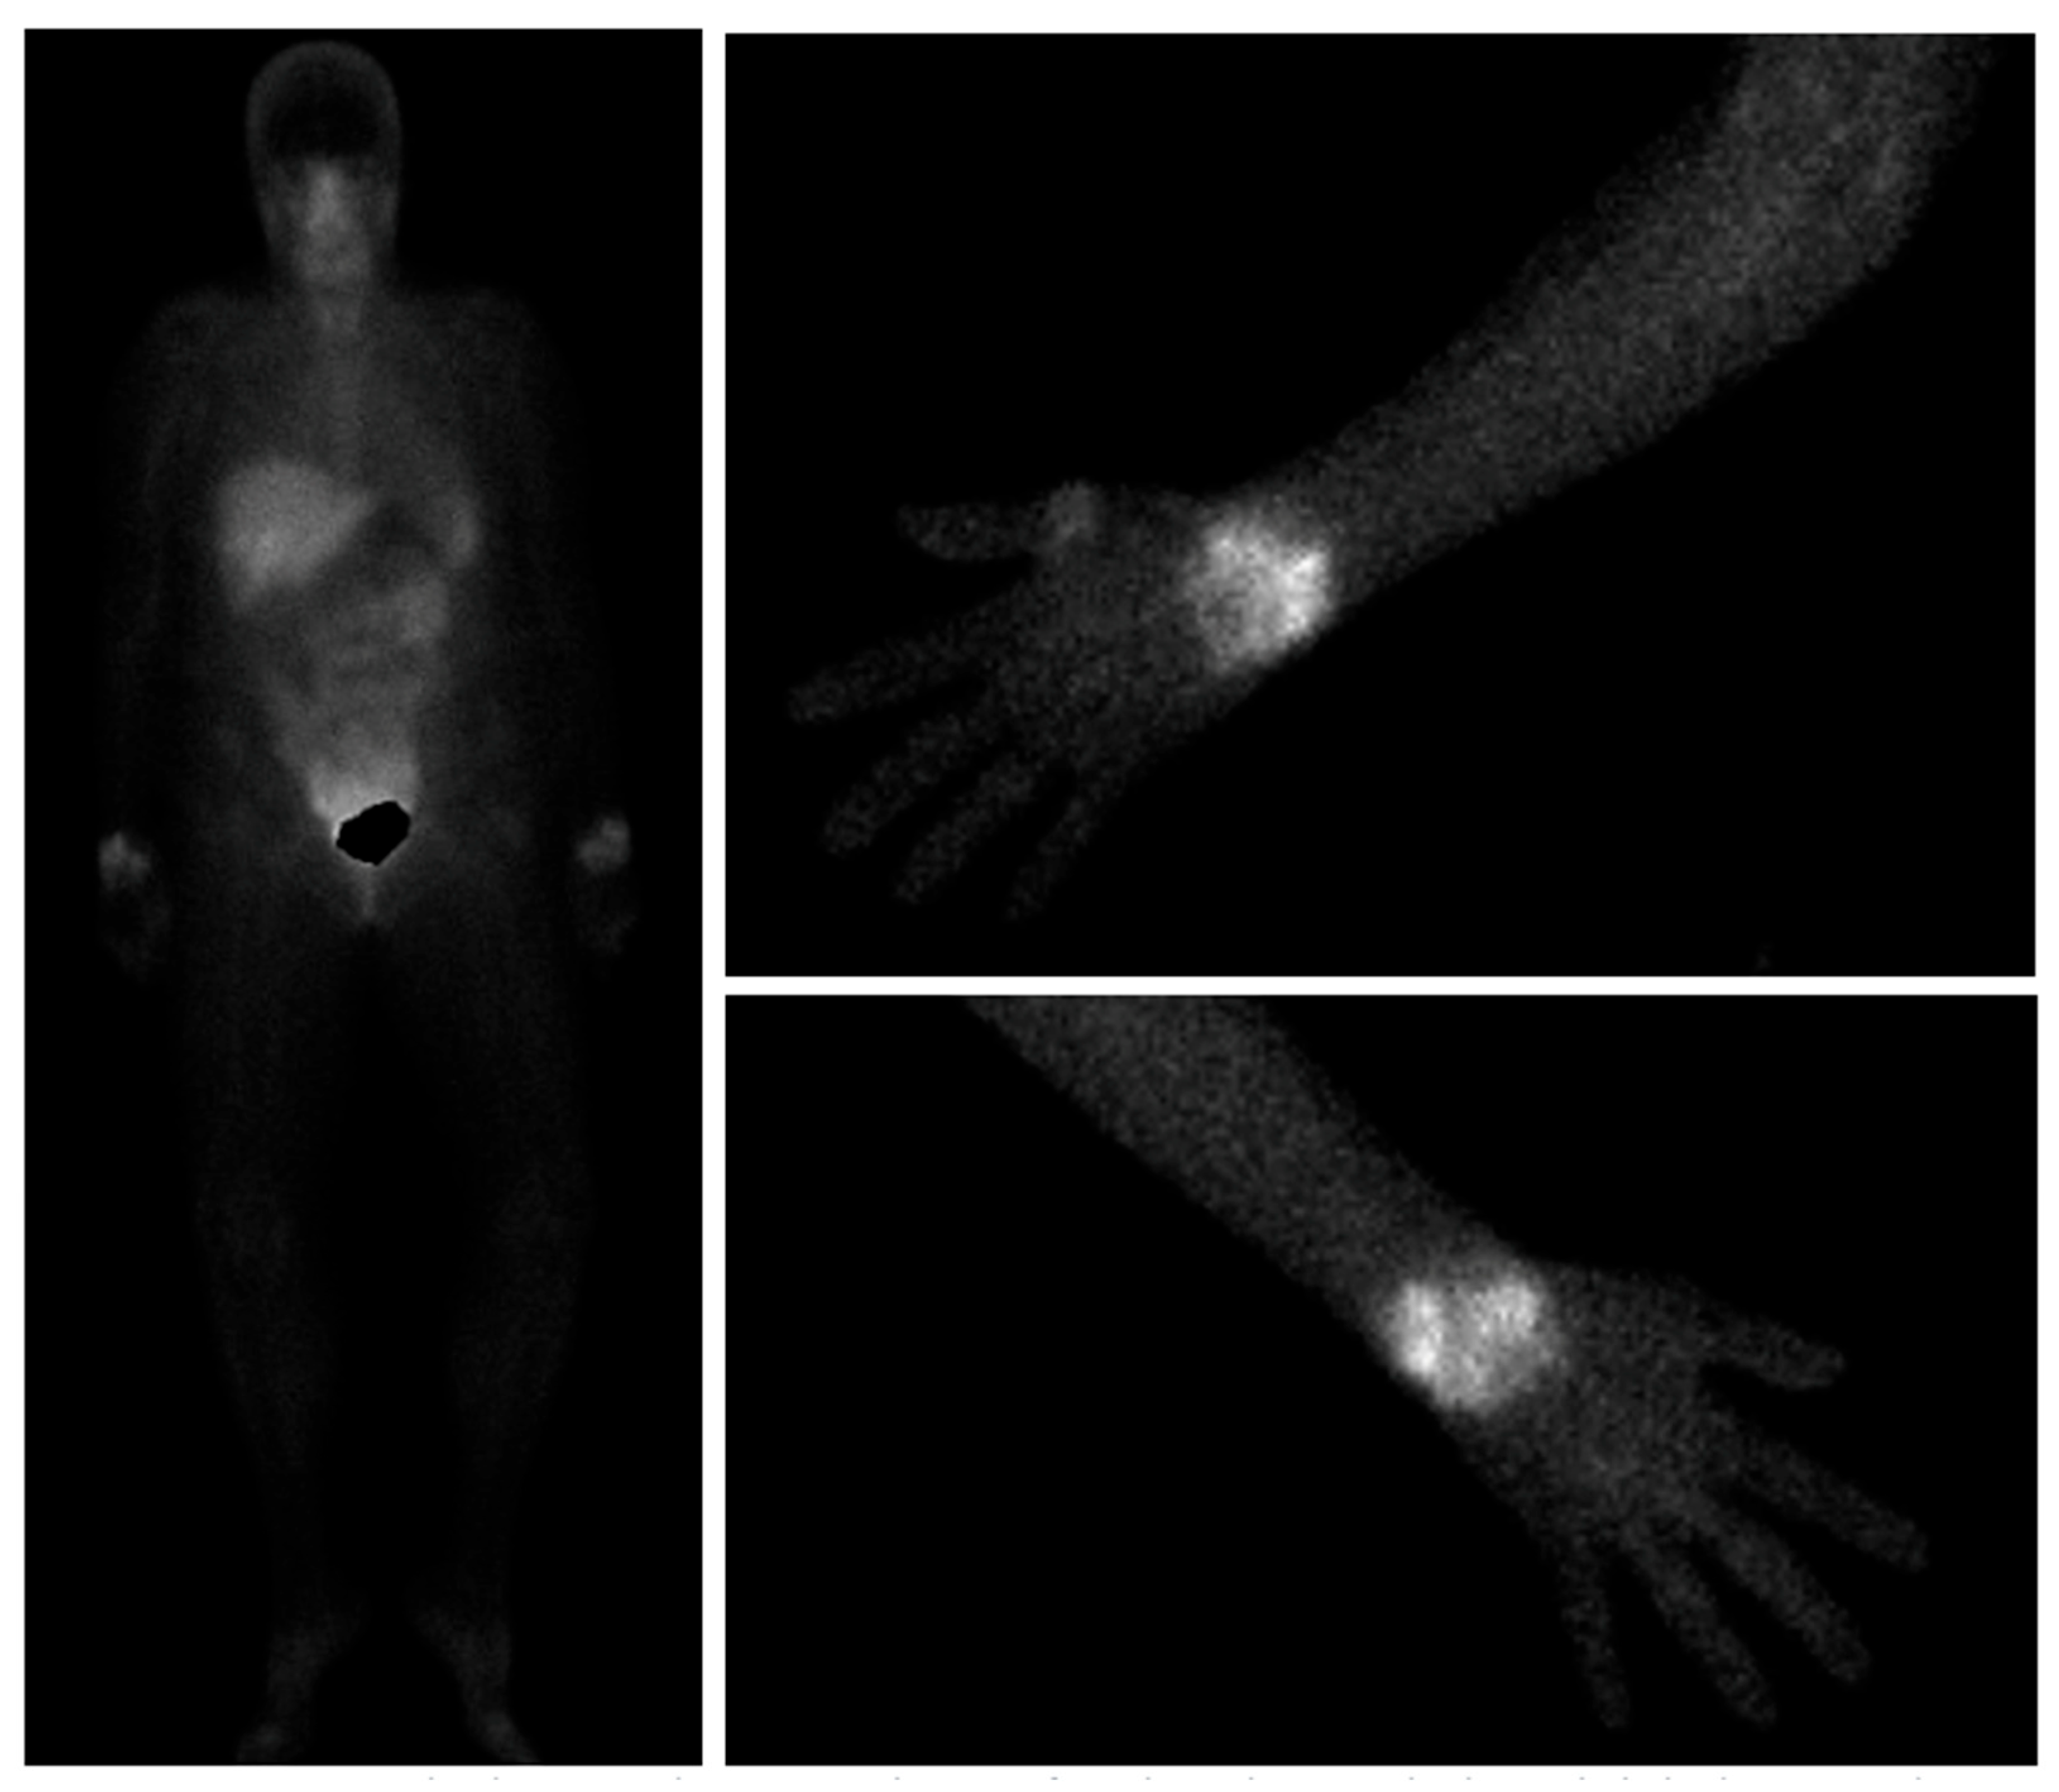

- Lee, S.J.; Hong, C.M.; Cho, I.; Ahn, B.-C.; Eun, J.S.; Kim, N.R.; Kang, J.W.; Kang, Y.M. Reappraisal of bone scintigraphy as a new tool for the evaluation of disease activity in patients with rheumatoid arthritis. Sci. Rep. 2021, 11, 21809. [Google Scholar] [CrossRef]

- Kim, J.Y.; Choi, Y.Y.; Kim, C.W.; Sung, Y.-K.; Yoo, D.-H. Bone Scintigraphy in the Diagnosis of Rheumatoid Arthritis: Is There Additional Value of Bone Scintigraphy with Blood Pool Phase over Conventional Bone Scintigraphy? J. Korean Med. Sci. 2016, 31, 502. [Google Scholar] [CrossRef]